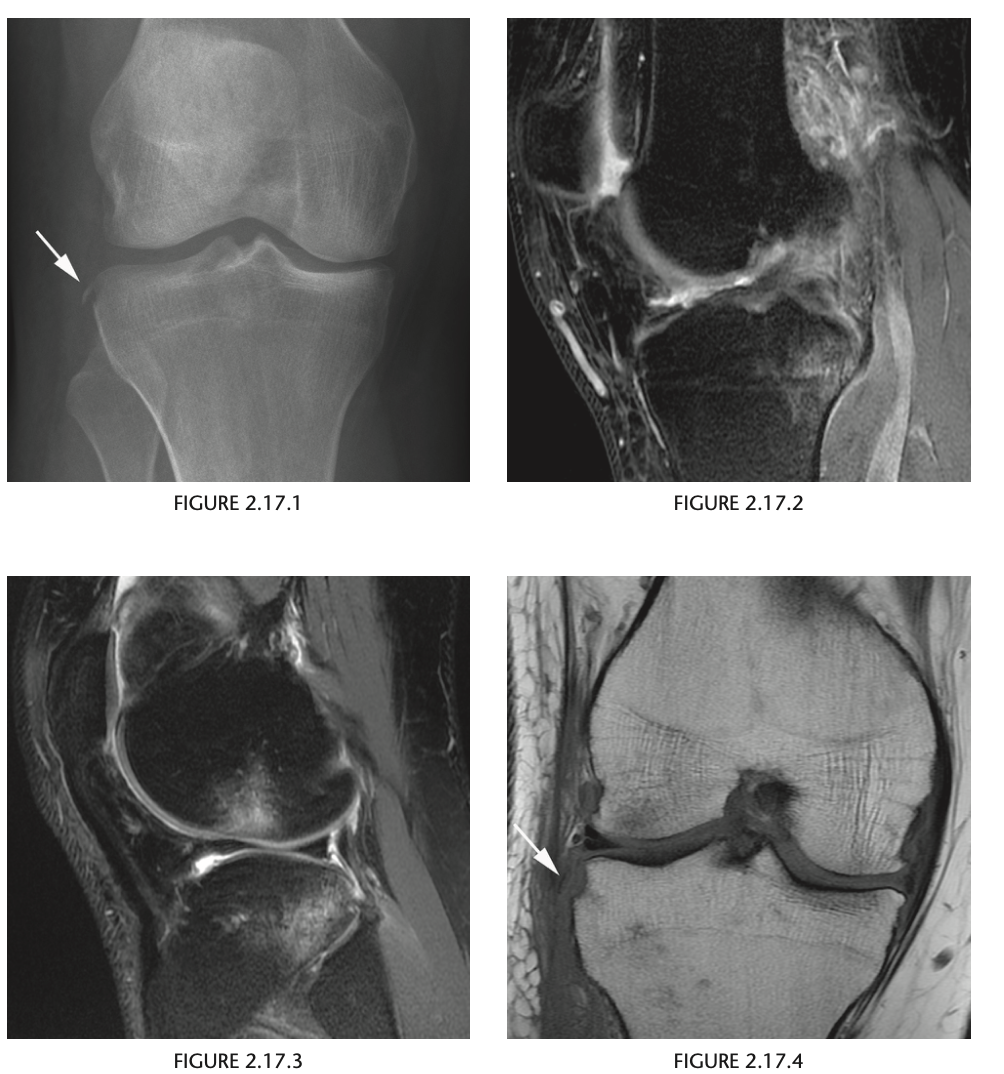

A 34-year-old man with an acute knee injury

Anteroposterior view of the right knee

shows a linear sliver of bone adjacent to the lat-

eral aspect of the lateral tibial plateau (Fig. 2.17.1,

arrow). A sagittal proton-density MR image of the

knee in the same patient shows an ACL tear and a

tibial plateau contusion.

Segond fracture

The avulsion

occurs posteriorly and proximal to Gerdy’s tubercle,

the insertion site of the iliotibial band, and is there-

fore classically thought to represent an avulsion frac-

ture of the lateral capsular ligament from its insertion

site on the lateral tibial plateau;

sagittal proton-density, fat-suppressed MR im-

age, shows “kissing contusions” typical for an ACL

tear. Figure 2.17.4, the coronal T1-weighted MR

image in the same patient, shows the small avul-

sion fracture fragment characteristic of the Segond

fracture. In most cases, however, trabecular micro-

fracture or bone marrow edema is seen adjacent

to the ­ avulsion fracture (74). A medial Segond-

type ­ fracture, a similar avulsion fracture affecting

the medial tibial plateau, has been described and

is ­ associated with injury to the posterior cruciate

ligament.